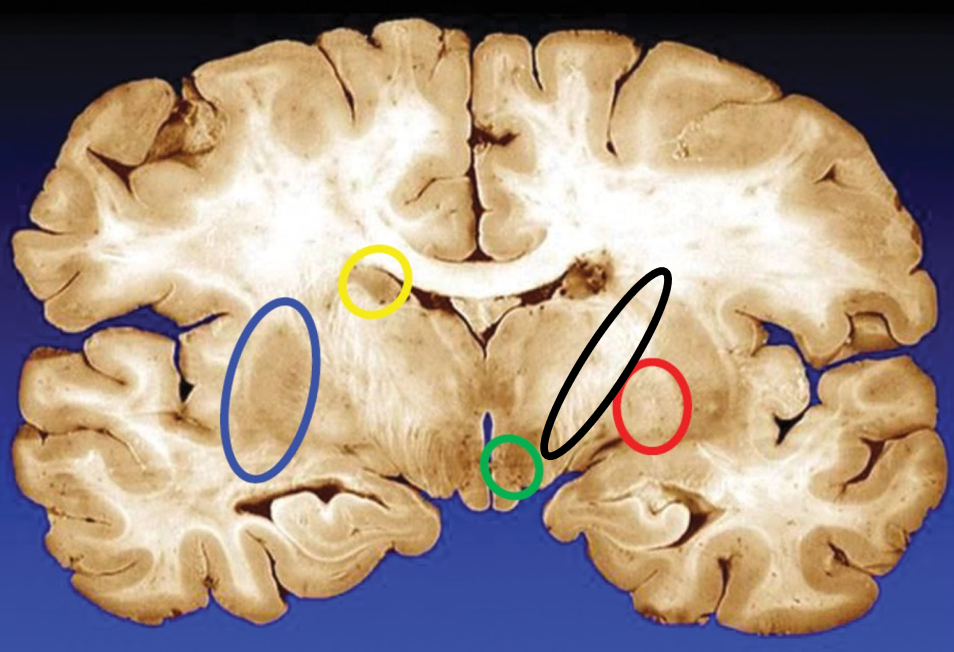

blue

putamen

yellow

caudate

green

subthalamic nuclei

black

internal capsule

red

globus pallidus

name the condition

Huntington’s (reduced caudate)